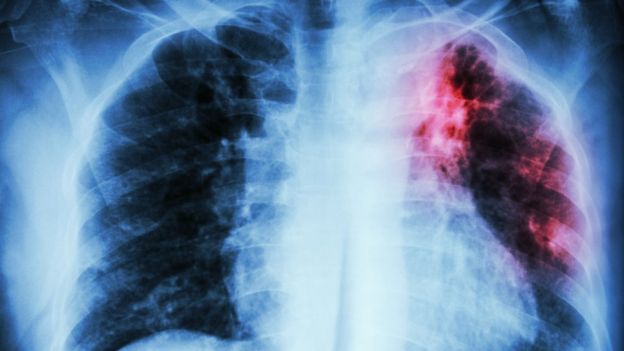

Existen 3 enfermedades infecciosas milenarias que siguen afectando a la población de América Latina. ¿Sabes cuáles son? (Foto Prensa Libre: Getty Images)

La tuberculosis es una enfermedad causada por la Mycobacterium tuberculosis, una bacteria que casi siempre afecta a los pulmones. Es curable y prevenible, señala la Organización Mundial de la Salud.

La tuberculosis se transmite de persona a persona a través del aire. Cuando un enfermo de tuberculosis pulmonar tose, estornuda o escupe, expulsa bacilos tuberculosos al aire. Basta con que una persona inhale unos pocos bacilos para quedar infectada, detalla la OMS.

Los síntomas pueden incluir tos, fiebre, sudores nocturnos y pérdida de peso y pueden ser leves durante muchos meses. Por eso, los pacientes tardan en buscar atención médica y transmiten la bacteria a otras personas.

Se calcula que una tercera parte de la población mundial tiene tuberculosis latente, es decir que esas personas están infectadas por el bacilo pero (aún) no han enfermado ni pueden transmitir la infección.

Y en el continente americano, la OPS estimó unos 282.000 casos nuevos y recaídas en 2017, que representa un 3% de la carga mundial de tuberculosis (10 millones de casos) y una tasa de incidencia de 28 por 100.000 habitantes.

En la región, la tasa de incidencia más alta se observó en el Caribe (61,2 por 100.000 habitantes), seguido de América del Sur (46,2), América Central y México (25,9) y Norte América (3,3).

“Pero es una enfermedad que desafortunadamente sigue siendo un importante problema de salud pública en el mundo porque por varias razones ha desarrollado mecanismos de resistencia a los medicamentos para tratarla y en casos combinados con VIH o desnutrición puede llegar a ser mortal”, dice Nicholls.